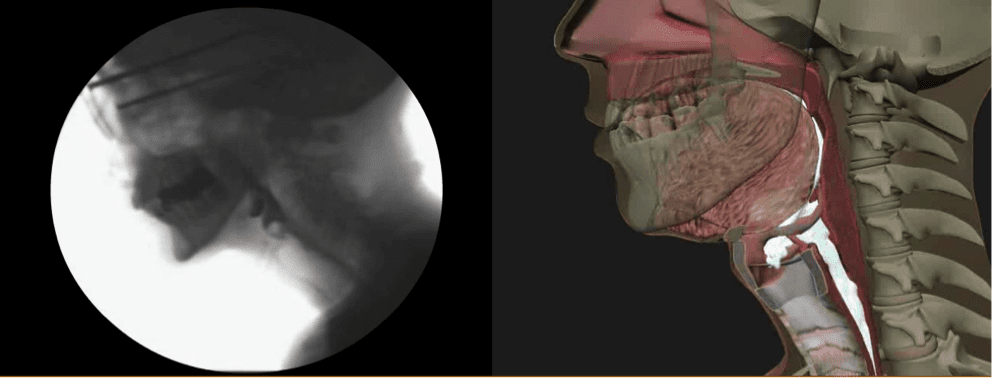

Home The Modified Barium Swallow Impairment Profile© (MBSImP™): Standardized training in swallowing physiology Image2

MBSImP Bonnie Martin-Harris